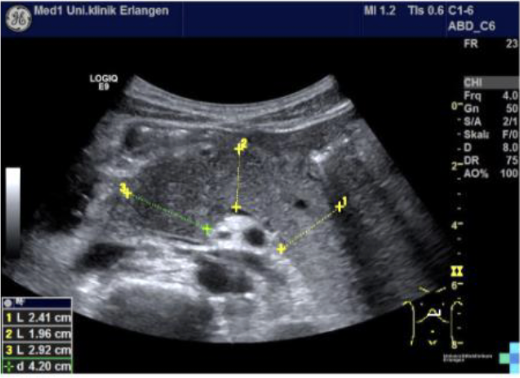

Path?

Acute Pancreatitis